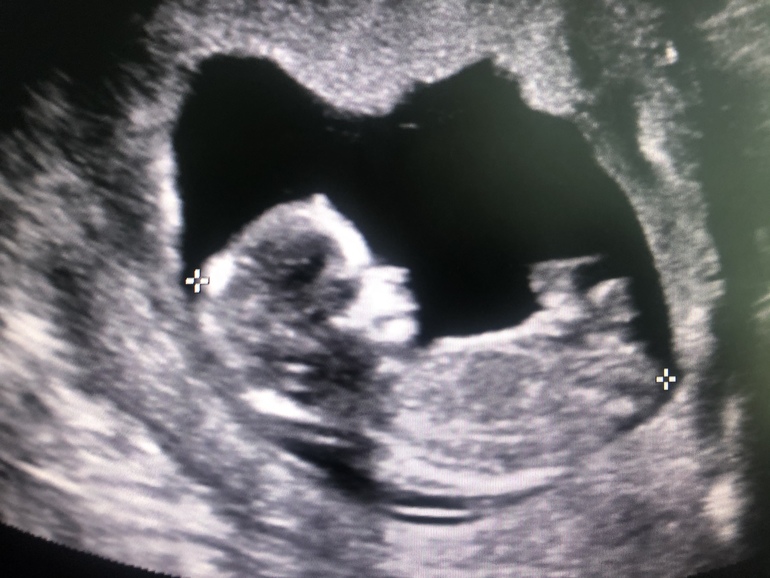

Ох , я даже и не думала , что повезёт и врач такой крутой попадётся! Все показал , минут 30 все смотрел со всех сторон. Крох лежал хорошо и было все замечательно видно. Нос блестит ярким пятном , ручками двигает, даже обе ручки показал. Ножки согнуты, поэтому уже там внизу не очень видно было.

Врач сказал , что ему все нравится и крох хорош)) ктр 70

Конечно)) он и сердце несколько раз включал , 153 удара было, и другое какое то шипение включал... он вообще все что можно делал)))